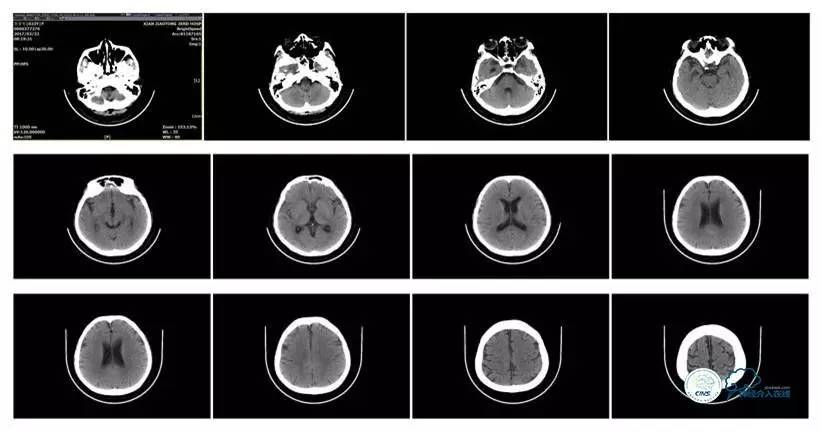

头颅CT

病史:患者于1年余前,因头部外伤在外院行头颅CT提示:未见异常。约3月后患者出现头痛、发作性意识丧失,在当地医院行头颅CT及MRI提示:未见明显异常。诊断为外伤性癫痫,予以对症治疗,未见明显好转。6月余前,无明显诱因出现鼻腔漏液,予以保守治疗,此后鼻腔间断漏液,漏液后头痛缓解。13天前因高热、恶心、呕吐在外院诊断为颅内感染(肺炎链球菌),予以抗炎等对症治疗2周后鼻漏停止,体温正常,CSF常规、生化正常,但头痛仍未缓解,转入我院神经内科治疗。反复腰穿颅内压450-500mmH2O左右,脑脊液常规及生化均正常。颅脑CT及MRI、MRV提示:左侧顶叶硬膜下血肿,鼻窦炎、乳突炎、左侧横窦、乙状窦闭塞、右侧横窦、乙状窦狭窄。予以华法林抗凝治疗2周,维持INR2-3,患者头痛仍无明显缓解,颅内压无降落,转入我科。

诊断:1、右侧横窦、乙状窦狭窄;2、硬膜下血肿(左侧顶);3、继发性癫痫;4、脑脊液鼻漏;5、颅内感染;6、乳突炎;7、鼻窦炎。

病理过程推理:首先是乳突炎—诱发左侧横窦乙状窦血栓最终闭塞,右侧横窦乙状窦狭窄—导致颅内高压,造成头痛及癫痫—持续颅内高压—皮层静脉回流受阻导致自发性硬膜下血肿及自发性脑脊液鼻漏—颅内感染。